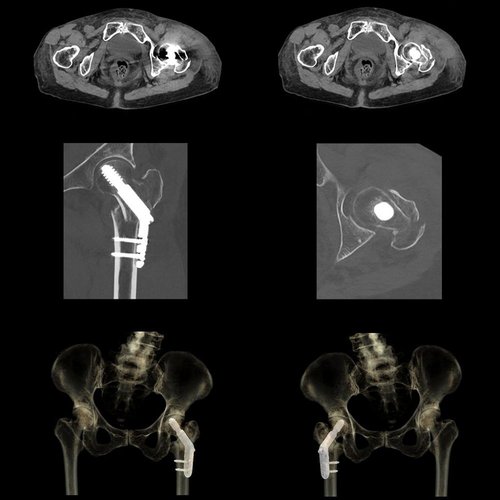

Bei dem Volumen-CT Aquilion One PRISM Edition von Canon Medical handelt es sich um einen einzigartigen HighEnd-Computertomographen. Er setzt während der DualEnergy-Akquisition und der Datenrekonstruktion neue Maßstäbe und greift in der spektralen Bildgebung auf die Deep-Learning-Rekonstruktion AiCE zurück.

Auch für virtuelle monochromatische Bilder mit 35 keV – 135 keV, die Reduktion von Beam-Hardening-Artefakten, Knochenentfernungen, die Bestimmung der Ordnungszahl, Electron-Density-Bestimmungen und viele andere Anwendungen bietet der Aquilion One PRISM Edition das optimale Gerät.

Mit AiCE, kurz für Advanced intelligent Clear-IQ Engine, kann der Aquilion One PRISM Edition besonders scharfe, klare und präzise Bilder in kürzester Zeit gewinnen. Die KI unterstützt die Reduktion von Bildrauschen auf ein Minimum und ermöglicht klare Aufnahmen mit sehr gut erkennbaren Strukturen auch bei niedrigem Kontrast. Gleichzeitig bringt sie eine automatische Anpassung des Kontrasts mit sich. Weiterhin ermöglicht sie eine schnelle kV-Umschaltung und eine patientenspezifische mA-Modulation, die wiederum mit einer Deep Learning-Rekonstruktion kombiniert wird, um eine hervorragende Energietrennung zu erzielen und Bildrauschen weiter zu reduzieren.